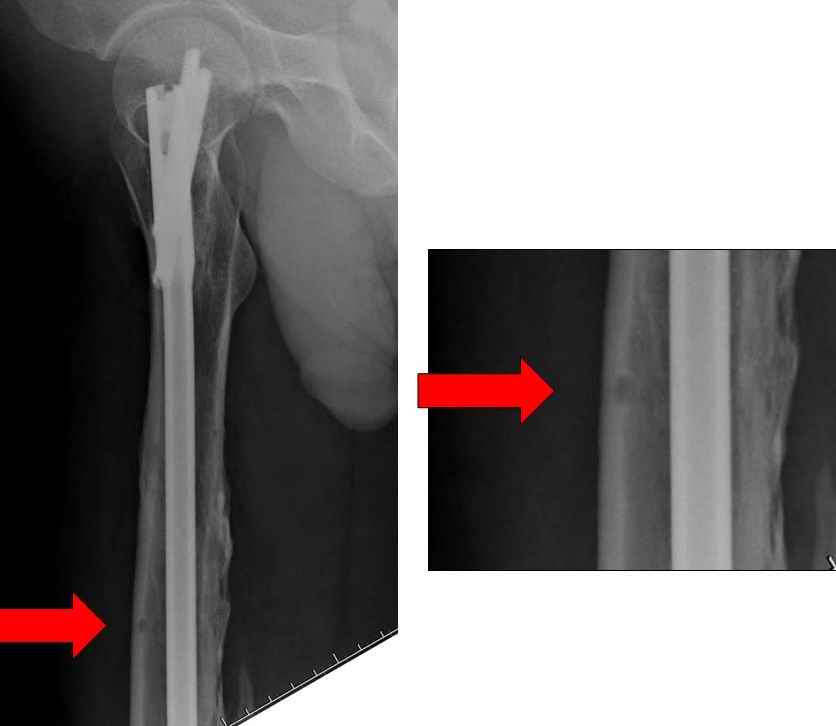

Снимок №4 сделан после несостоятельности интрамедуллярного штифта, осложнения инфекцией канала и после миграции шурупов. Я имел ввиду, что снимок № 2 после удаления наружного фиксатора в интрамедуллярном варианте, на увеличенном снимке дырка на переднем кортексе (см. снимок) stress zone Чтобы правильно без осложнений провести half pins, необходимо соблюсти нескольких правил, во первых, они должны вводится в середине диаметра кости с предварительным просверливанием. Во время просверливания кости, сверло проходит первый, потом второй дальний кортекс и стержен вводится вручную. А иногда сверление проходит по касательной к кортексу, нагреваются местные ткани, создается ожог и локальный некроз. Или как будто делается кортикотомия с помощью сверла, как при

методе Илизарова, ослабляя кортикальный слой. Создается стрессовая зона, которая при незначительной травме может осложниться стрессовым

переломом.